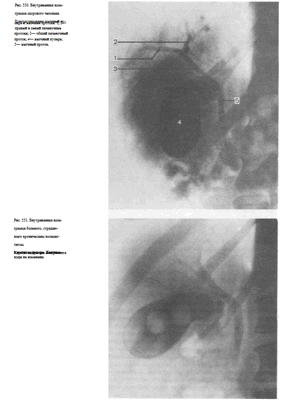

У здоровых людей на холецистограммах определяется интенсивная однородная тень желчного пузыря с четкими контурами (рис. 547).

При калькулезных холециститах тень пузыря менее интенсивна, в проекции пузыря определяются дефекты наполнения, образованные камнями(рис. 548).

Для оценки сократительной и эвакуационной функции желчного пузыря после выполнения снимков (при наличии на них отображения тени желчного пузыря) больному дают желчегонный завтрак (сырые желтки, сливочное масло, сорбит) и спустя 20 и 50 мин делают прицельные снимки (рис. 549).

При выделительной холецистохолангиографии на снимках отчетливо видны печеночные протоки, общий желчный проток, пузырный проток, а также желчный пузырь (рис. 550). Интенсивность выделения препарата печенью характеризует и ее выделительную функцию.

Выделительная холеграфия дает возможность выявить холестериновые камни как желчного пузыря, так и расположенных в желчных протоках, а также исследовать желчные пути после холецистэктомии (рис. 551).